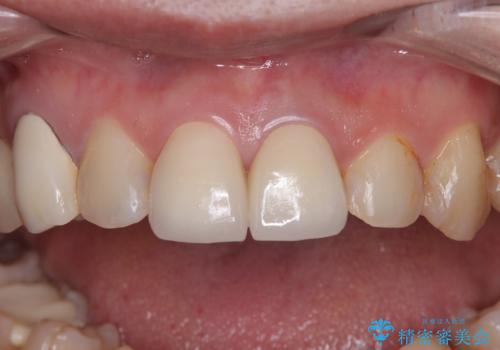

神経が露出しないよう慎重に行った結果、神経を保存することができました。処置後に多少の痛みが生じましたが、その後は良好な状態が続いています。

色、形ともに、自然な仕上がりとなり、患者様には大変満足していただきました。